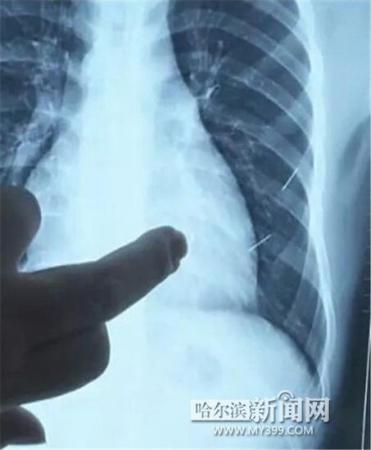

医生指出X光片上的针状物

昨日上午,记者在哈医大二院第八住院部心外三病房找到了躺在病床上痛苦不堪的董立仁,家属正在他身旁不断安慰着他。见记者前来,董立仁母亲李百燕拿出一张X光片,上面可以清晰地看到胸腔内一共有4根针状物,其中一根在心脏部位,两根在胸腔壁上,还有一根在腹腔壁上。